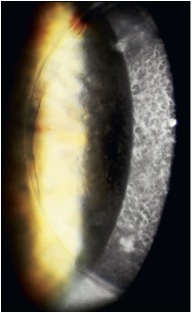

what is lattice dystrophy (type 1)?

age 2-10, VA reduction, RCE common anterior stromal “inter-lacing” filamentous lesions, white spots, central haze (amyloid deposits)